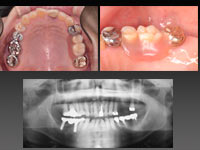

重度歯周炎(侵襲性歯周炎)の治療(16年経過)です。一部は歯周外科を行いました。